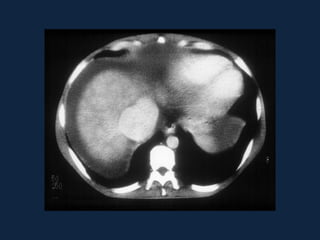

►s/c: Lesão grosseiramente arredondada, hipodensa

(0-45 HU), podendo conter septações e gás (sinal

específico, presente em menos de 20% dos casos).

Pode haver nível ar-fluido e fluido-debris.

►Realce anelar e/ou das        septações   após   a

administração do contraste.

►Pode haver derrame pleural e atelectasia de lobo

inferior direito.

Abscessos Piogênicos

 S/C                 Fase portal